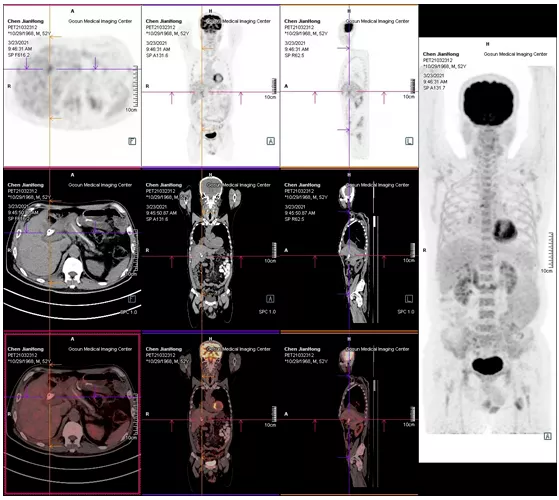

2021年05月 PET/CT檢查結(jié)果

復查PET-CT提示原術(shù)區(qū)復發(fā)病灶、肝內(nèi)轉(zhuǎn)移灶、右側(cè)胸膜轉(zhuǎn)移灶控制良好

治療效果評估

用藥3個月后,患者精神狀態(tài)明顯好轉(zhuǎn),食欲改善,體重增加,腫瘤指標下降,PET/CT結(jié)果提示,無明顯腫瘤復發(fā)或轉(zhuǎn)移征象,肝內(nèi)腫瘤活性已受抑制。